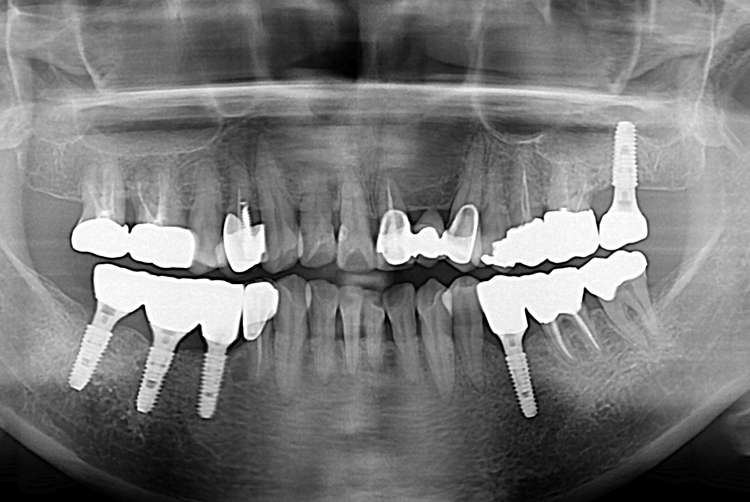

[임플란트] 어금니 임플란트

치료전 : 2017-05-30